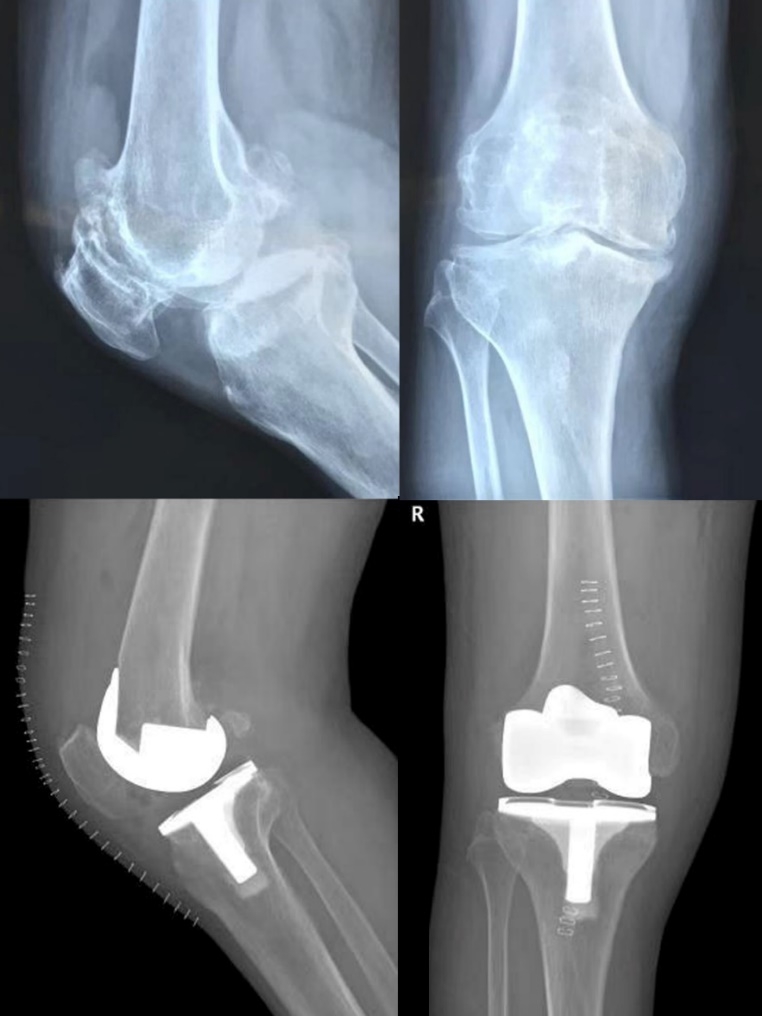

2019年8月13日和9月12日,由科室主任史占军教授主刀,为3位饱受膝关节炎病痛折磨的患者实施了全膝关节置换手术,术中首次使用了安择™膝关节,再次证明了施乐辉国产膝关节与一直以来提供的进口假体有着同样的品质。

史占军教授手术后对此款假体感受颇深,最大的改进在于前髁收窄设计,能够避免前髁的悬挂以及对周围软组织的刺激,它在假体和工具的设计上都给我们提供很好的帮助,这是南方医科大学南方医院的首款国产膝关节假体,相信它将是一个新的里程碑。

患者术前术后光片